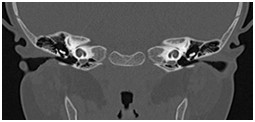

颞骨及耳(病例-前庭导水管扩大)